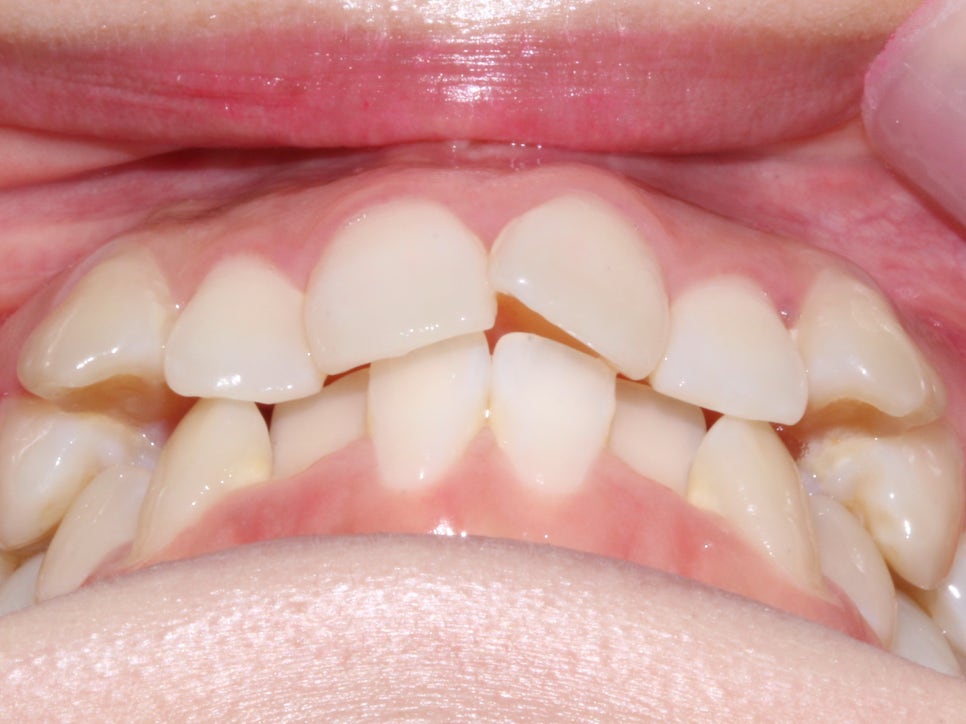

돌출입, 덧니교정 2D교정으로 진행 (전 사진)

돌출입, 덧니치아 2D교정으로 완성! by.투디치과(2D치과)

상악과 하악의 교합면이 고르지 못하고

덧니로 인해 치열에 총생이 생겨

심미적으로 좋지 못한 상태입니다.

하악의 경우 덧니로 인해 치아 사이의 공간이

매우 좁아 전치부의 치아가

삐뚤빼뚤해 보이기까지 합니다.